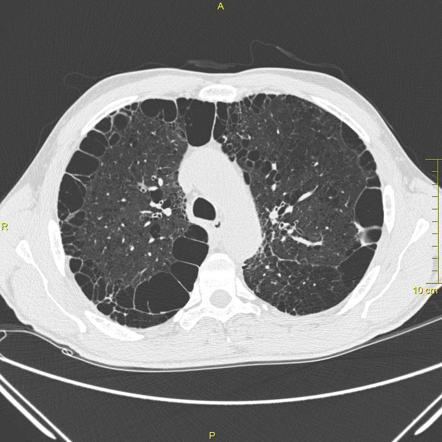

Subpleural bullae